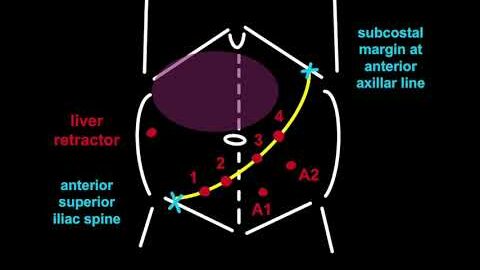

Port Placements by Indian (Manipal) Modification for da Vinci X Surgical System

Gynecology, Oncology ';